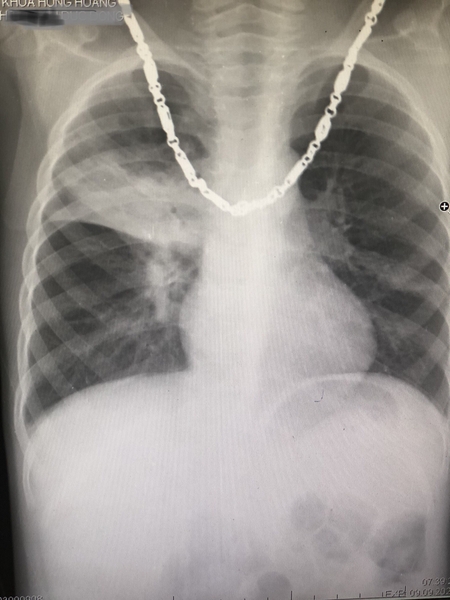

PHÁT HIỆN TRƯỜNG HỢP VIÊM PHỔI THÙY Ở TRẺ 5 TUỔI

Vừa rồi Hồng Hoàng khám và điều trị cho bệnh nhân nhi 5 tuổi với triệu chứng sốt, ho. Sau quá trình khám bệnh, nghe tim phổi, cho làm xét nghiệm máu và chụp x-quang tim phổi nhận thấy cháu bị viêm phổi thùy. Bác sĩ đã cho cháu đơn thuốc điều trị phù hợp.